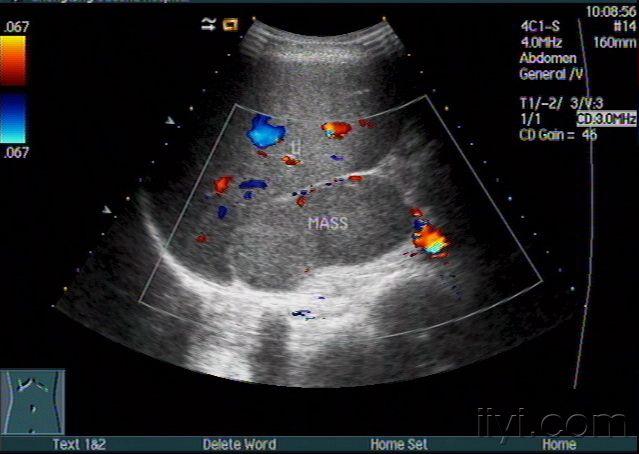

肾上腺彩超

肾上腺超声

肾上腺正常解剖及疾病超声诊断

肾上腺病变大家讨论 - 超声医学讨论版 - 爱爱医医学论坛-爱爱医医学

超声诊断肾上腺转移ca声像图表现zengerya